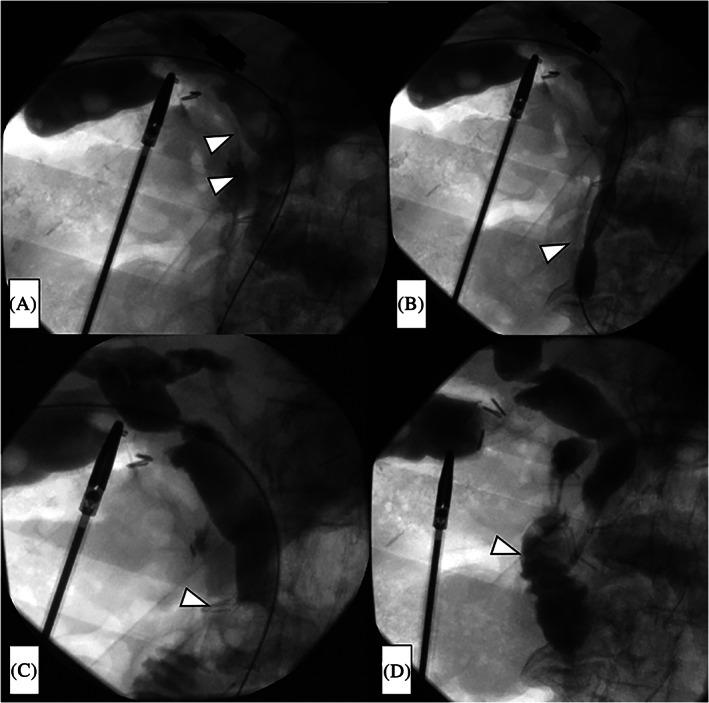

After contrast medium was injected into the bile duct from the sheath and the presence of choledocholithiasis was confirmed (Figure 2A), the papilla of Vater was dilated using a TMP balloon catheter (10 × 40 mm; 7 atm, 3 minutes) (Tokai Medical Products, Aichi, Japan) (Figure 2B).

A Selecon MP Catheter (Terumo Europe NV) was then inflated upstream of the choledocholithiasis, after which the stones were extruded using the catheter balloon and the CBD was cleaned (Figure 2C). This procedure was repeated three times.

After the CBD was cleaned, the absence of residual stones was confirmed by a final cholangiogram, and a pigtail‐shaped drainage catheter (UreSil, Skokie, Illinois) was placed at the papilla of Vater to prevent edema of the papilla of Vater and subsequent pancreatitis (Figure 2D). This drainage catheter easily falls into the duodenum when oral feeding is commenced. Finally, we removed the balloon catheter system, closed the cystic duct with clips, and extracted the gallbladder in the usual manner.